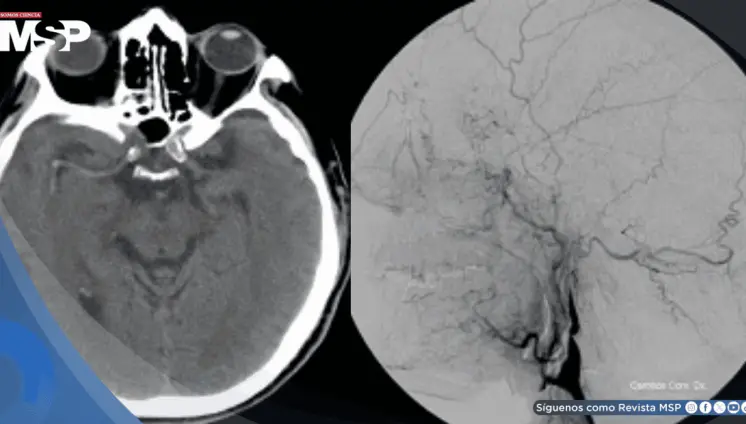

El aneurisma, detectado mediante una resonancia magnética, representaba un alto riesgo de ruptura y muerte, lo que obligó a una intervención urgente.

Un inusual caso de malformación vascular mandibular (AVM) en una gestante de 39 semanas derivó en una hemorragia potencialmente mortal y parto por cesárea de emergencia.

La clave estaba en entender que la tos violenta había generado una presión súbita en las arterias del cuello, causando un desgarro en la pared interna de la arteria carótida derecha.

Un caso médico inusual revela cómo la migraña común puede evolucionar hacia una forma devastadora y poco frecuente